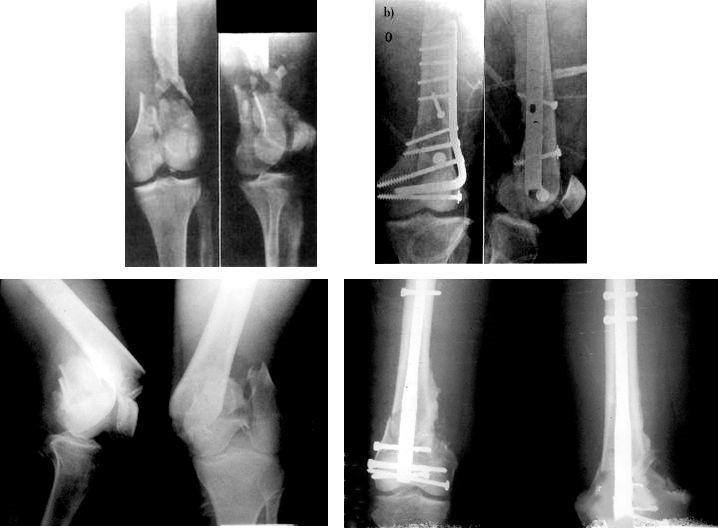

Patients présentant de graves lésions des tissus mous, des fractures ouvertes ou des difficultés lors d'une opération précoce - Fixateur externe super-articulaire.

Traitement chirurgical immédiat d'une lésion isolée - DCS, clou centromédullaire rétrograde.

L'état général du patient est stable et les conditions cutanées locales le permettent, l'opération doit être effectuée immédiatement.

Déterminer la nature de la violence liée aux blessures

Les blessures à haute énergie sont souvent accompagnées de lésions graves des tissus mous.Elle se caractérise par un gonflement des membres, des cloques, une abrasion cutanée et une lacération cutanée.L'opération doit être reportée pour le moment.Dans le même temps, le syndrome de l'espace fascial et les lésions vasculaires et nerveuses doivent être exclus.

La particularité de l'anatomie - l'importance de la couverture des tissus mous.

Stade précoce : dans les 8h